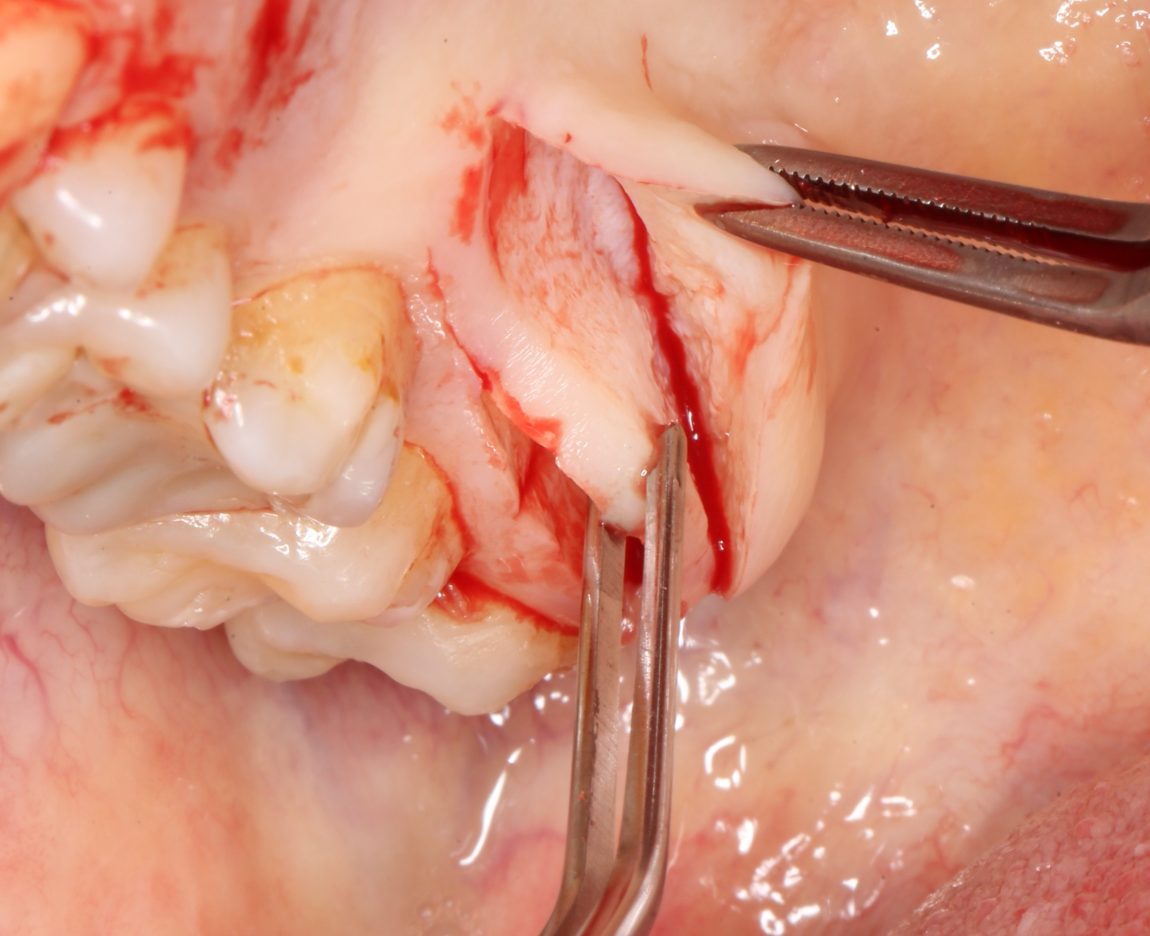

Следующий шаг — подготовка ложа под соединительнотканный аутотрансплантат или, проще говоря — под пересадку десны. Мы решили минимизировать травму, поэтому будем создавать подслизистый тоннель:

Это довольно просто, хотя и требуется известная аккуратность. Мы используем обычные инструменты для синуслифтинга:

Вы уже догадались, что мы не планируем дополнительных разрезов — весь объём работы мы проведём через лунки зубов. Таким образом, мы снизим травматичность нашей операции и, как следствие, риск возможных осложнений.

Создание тоннеля в области центральных резцов занимает 10-15 минут. В последующем, мы проведём и зафиксируем в нём соединительнотканный аутотрансплантат, который создаст необходимый для эстетики объём мягких тканей: